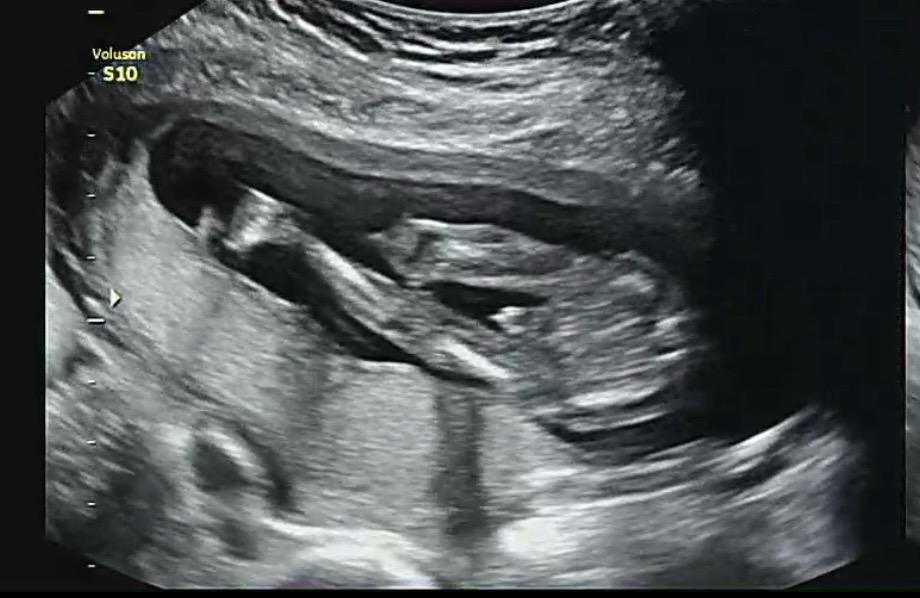

아들 확정!!

존재감 확실하지 않나용??🤭